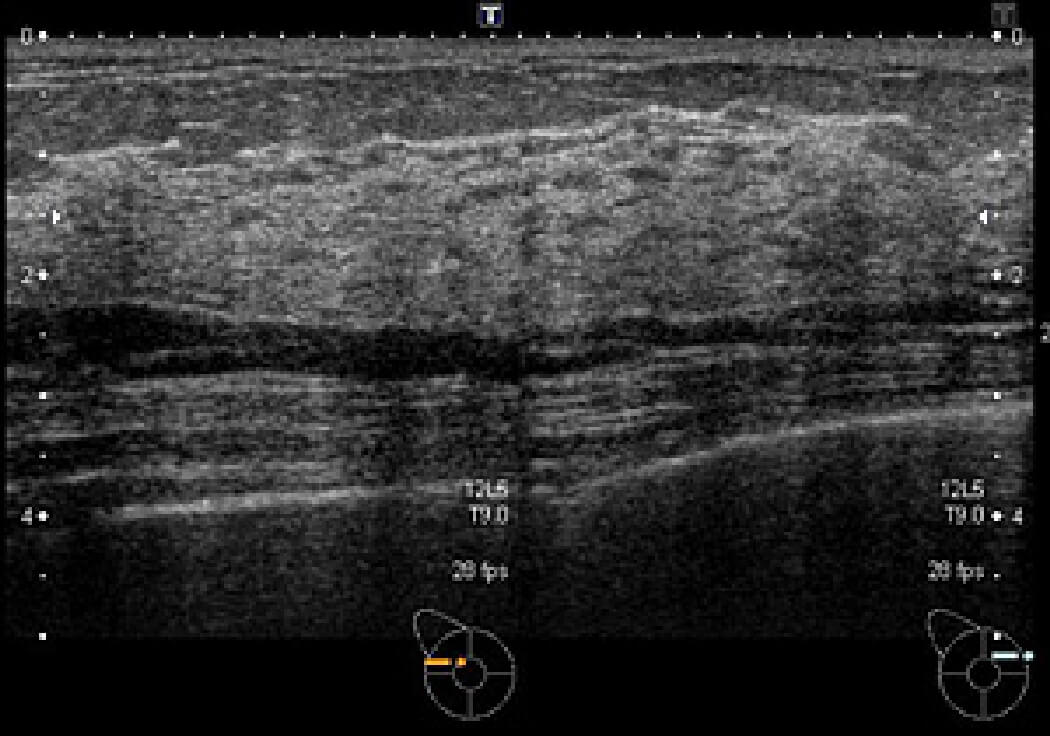

乳房超音波検査

正常